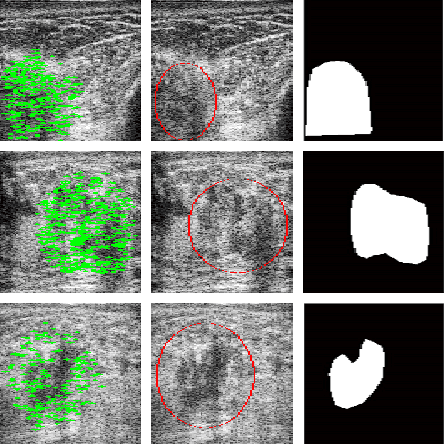

Abstract:Recent advances in using quantitative ultrasound (QUS) methods have provided a promising framework to non-invasively and inexpensively monitor or predict the effectiveness of therapeutic cancer responses. One of the earliest steps in using QUS methods is contouring a region of interest (ROI) inside the tumour in ultrasound B-mode images. While manual segmentation is a very time-consuming and tedious task for human experts, auto-contouring is also an extremely difficult task for computers due to the poor quality of ultrasound B-mode images. However, for the purpose of cancer response prediction, a rough boundary of the tumour as an ROI is only needed. In this research, a semi-automated tumour localization approach is proposed for ROI estimation in ultrasound B-mode images acquired from patients with locally advanced breast cancer (LABC). The proposed approach comprised several modules, including 1) feature extraction using keypoint descriptors, 2) augmenting the feature descriptors with the distance of the keypoints to the user-input pixel as the centre of the tumour, 3) supervised learning using a support vector machine (SVM) to classify keypoints as "tumour" or "non-tumour", and 4) computation of an ellipse as an outline of the ROI representing the tumour. Experiments with 33 B-mode images from 10 LABC patients yielded promising results with an accuracy of 76.7% based on the Dice coefficient performance measure. The results demonstrated that the proposed method can potentially be used as the first stage in a computer-assisted cancer response prediction system for semi-automated contouring of breast tumours.

Abstract:Quantitative ultrasound (QUS) methods provide a promising framework that can non-invasively and inexpensively be used to predict or assess the tumour response to cancer treatment. The first step in using the QUS methods is to select a region of interest (ROI) inside the tumour in ultrasound images. Manual segmentation, however, is very time consuming and tedious. In this paper, a semi-automated approach will be proposed to roughly localize an ROI for a tumour in ultrasound images of patients with locally advanced breast cancer (LABC). Content-based barcodes, a recently introduced binary descriptor based on Radon transform, were used in order to find similar cases and estimate a bounding box surrounding the tumour. Experiments with 33 B-scan images resulted in promising results with an accuracy of $81\%$.